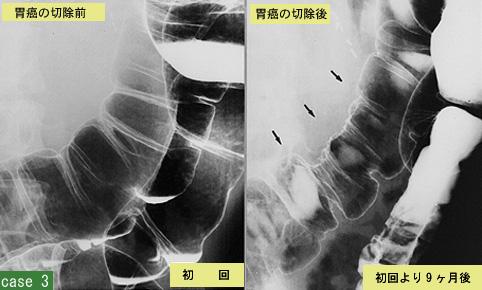

질환(병리주체)의 분류 전이성종양/

부위(장기별) 대장/횡행

검사방법 X-P

종양의 최대경(밀리미터) 40이상